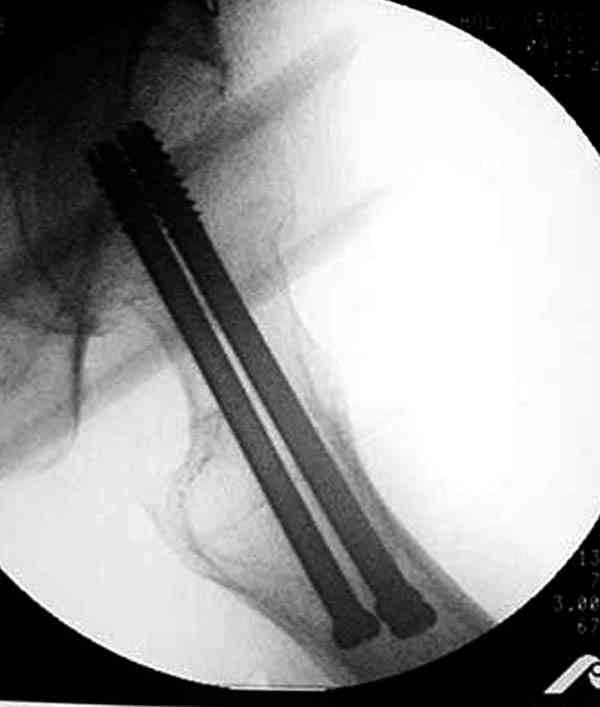

Коллега Челноков прав, здесь еще имеется риск перелома за счет ослабления латерального кортекса. Во время установки канюлированных шурупов за редким исключением спица вводится с одного раза, множественные попытки ослабляют латеральный кортекс, что станет источником перелома в этом месте.

В идеале для профилактики рефрактуры шурупы надо вводить не больше, чем под 130 градусным углом и не ниже уровня малого вертела.

Насчет биомеханических преимуществ одного шурупа  тоже возникает вопрос. Если придерживаться канонов механики, для перелома шейки необходимо 3 паралельных шурупа, расположенных ближе к кортикальному слою шейки.

Здесь случай перелома из-за ослабления латерального кортекса через 3 недели после операции на шейке. Шурупы были установлены под большим углом, слабый латеральный кортекс не выдержал нагрузку.